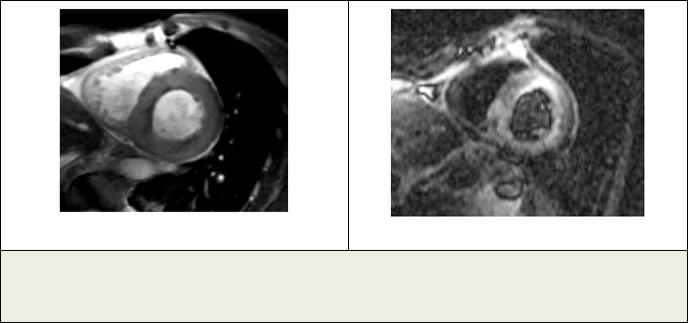

Рис. 3. МРТ.

а - МРТ сердца, Т2-ВИ. Короткая ось ЛЖ. Пациент Х., ОИМ. Видна зона отека; б – МРТ сердца с отсроченным контрастированием. Короткая ось ЛЖ. В области отека определяется трансмуральное контрастирование миокарда.